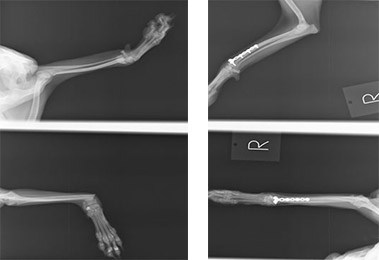

前肢橈尺骨骨折

1kg〜4kgの超小型犬が、室内でソファや抱っこの状態から飛び降りるくらいのことで骨折する場合が多いです。特に人気犬種のTプードルやチワワなどに多く認められます。

手術前

手術後

1.6kgのトイプードルの橈尺骨骨折です。プレートおよびスクリューを用いて固定、治療しました。